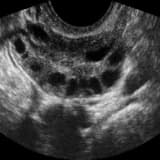

Ülkemizde geçmiş yıllarda, aslında cerrahi müdahale gerektirmeyen basit yumurtalık kistleri nedeniyle pek çok genç kız gereksiz yere ameliyat edilmiştir. Bu süreçte sadece kistin alınması yerine, bazen yumurtalığın tamamı veya bir kısmı alınarak büyük bir kayıp yaşatılmıştır. Hatta apandisit ameliyatları sırasında tesadüfen görülen ve aslında her kadında bulunması gereken follikül (yumurta içeren yapılar), kist sanılarak hatalı şekilde alınmıştır.

Son yıllarda özellikle endometriozis hastalığına bağlı gelişen ve çikolata kisti olarak bilinen endometriomalar için yapılan ameliyatlar, yumurtalık dokusuna ciddi zararlar vermektedir. Aşağıdaki durumlarda yapılan müdahaleler yumurta deposunu hızla tüketebilmektedir:

| Küçük Endometriomalar | Belirli bir büyüklüğe ulaşmamış kistlerin erkenden ameliyat edilmesi. |

| Geçici Kistler | 1-2 ay içinde kendiliğinden kaybolabilecek kistlerin alınması. |

| Dermoid Kistler | Cerrahi sırasında sağlıklı yumurtalık dokusunun korunmaması. |